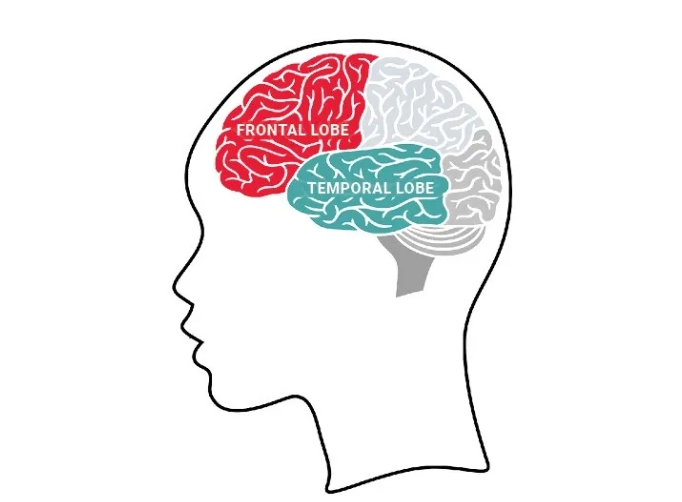

与首先损害记忆的阿尔茨海默病不同,额颞叶痴呆主要侵袭额叶和颞叶——这些区域位于前额后方及双耳上方,负责人格特征、行为调控和语言功能。一旦受损,患者可能出现性格突变、冲动控制障碍、语言理解或表达受限,甚至逐渐丧失沟通能力。

额颞叶痴呆主要侵袭额叶(红色示意)和颞叶(绿色示意)来源: Mike Mooney AFTD, CC0, https://commons.wikimedia.org/w/index.php?curid=166897324